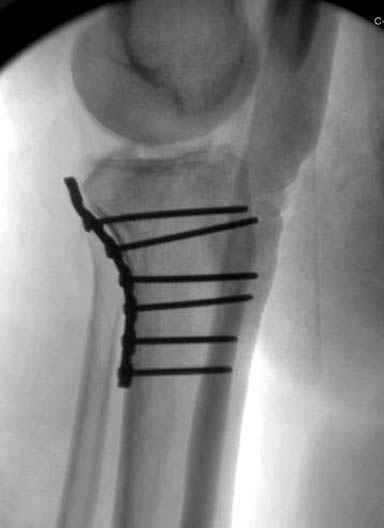

Надеюсь, представленные снимки разных случаев помогут разобраться в тактике, и критика примется без личной обиды.

Вложение не в текстовом формате было извлечено…

Имя     : 13 Med plateau fx.JPG

Тип     : image/jpeg